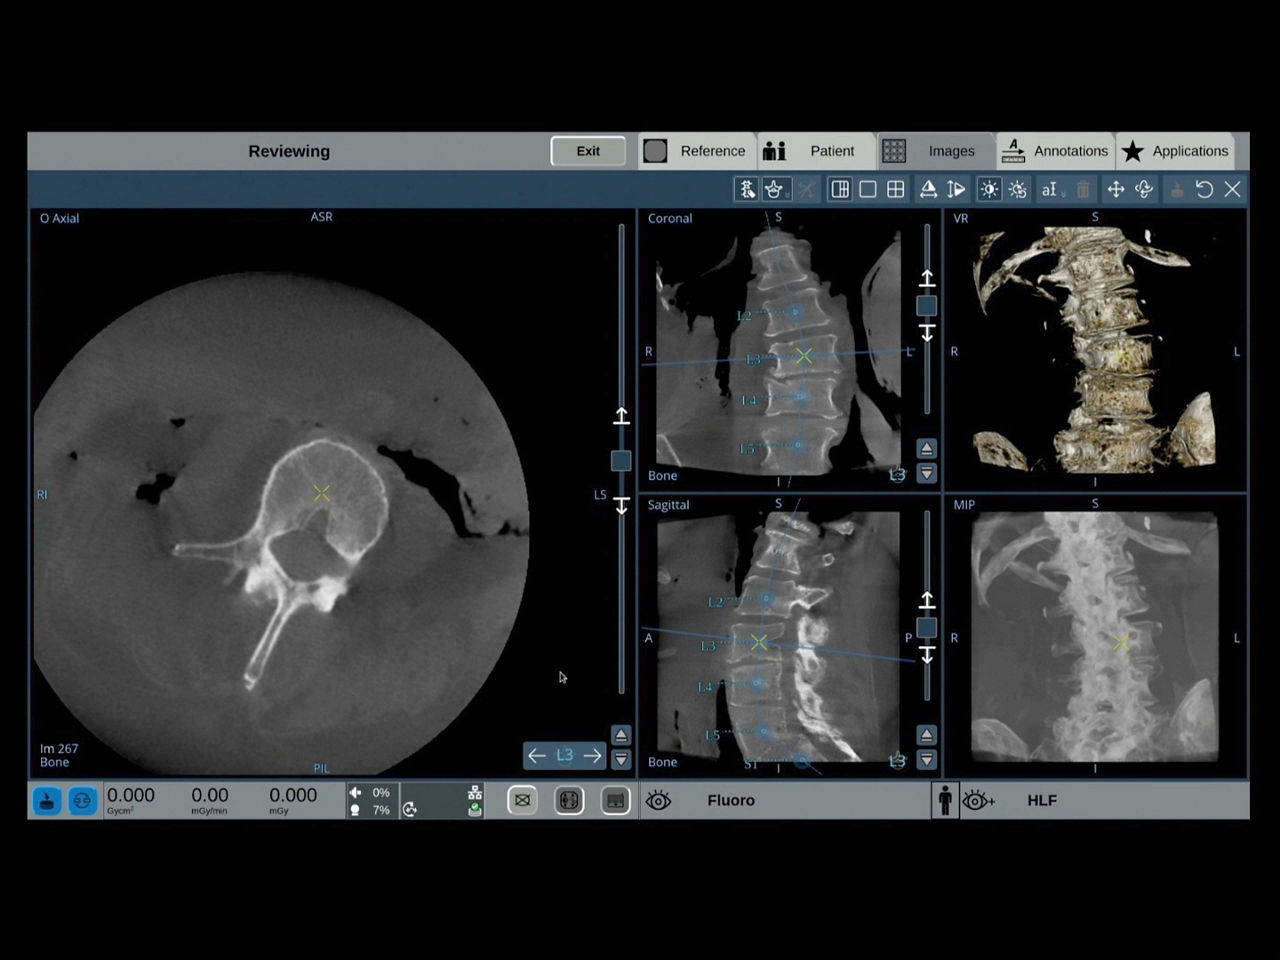

With OEC 3D, comprehensive imaging coverage of 19 cm x 19 cm x 19 cm 3D volumes and exceptional 2D images enables viewing several levels of the spine in the operating room.

The OEC 3D presents five perspectives: Axial, Coronal, Sagittal, MIP, and VR, on a 4K display for clear and detailed review of 3D volumes and 2D images

Analyze CT-like images with the OEC 3D Volume Viewer which includes Multi-Oblique, Area Measure, Window Level/Window Width, rotate, zoom, and more for quick and comprehensive visualization.

Review screws with automatic detection and numbering, manually label spine levels, and visualize spinal curvature alignment with Spine Suite, an optional application available with OEC 3D.